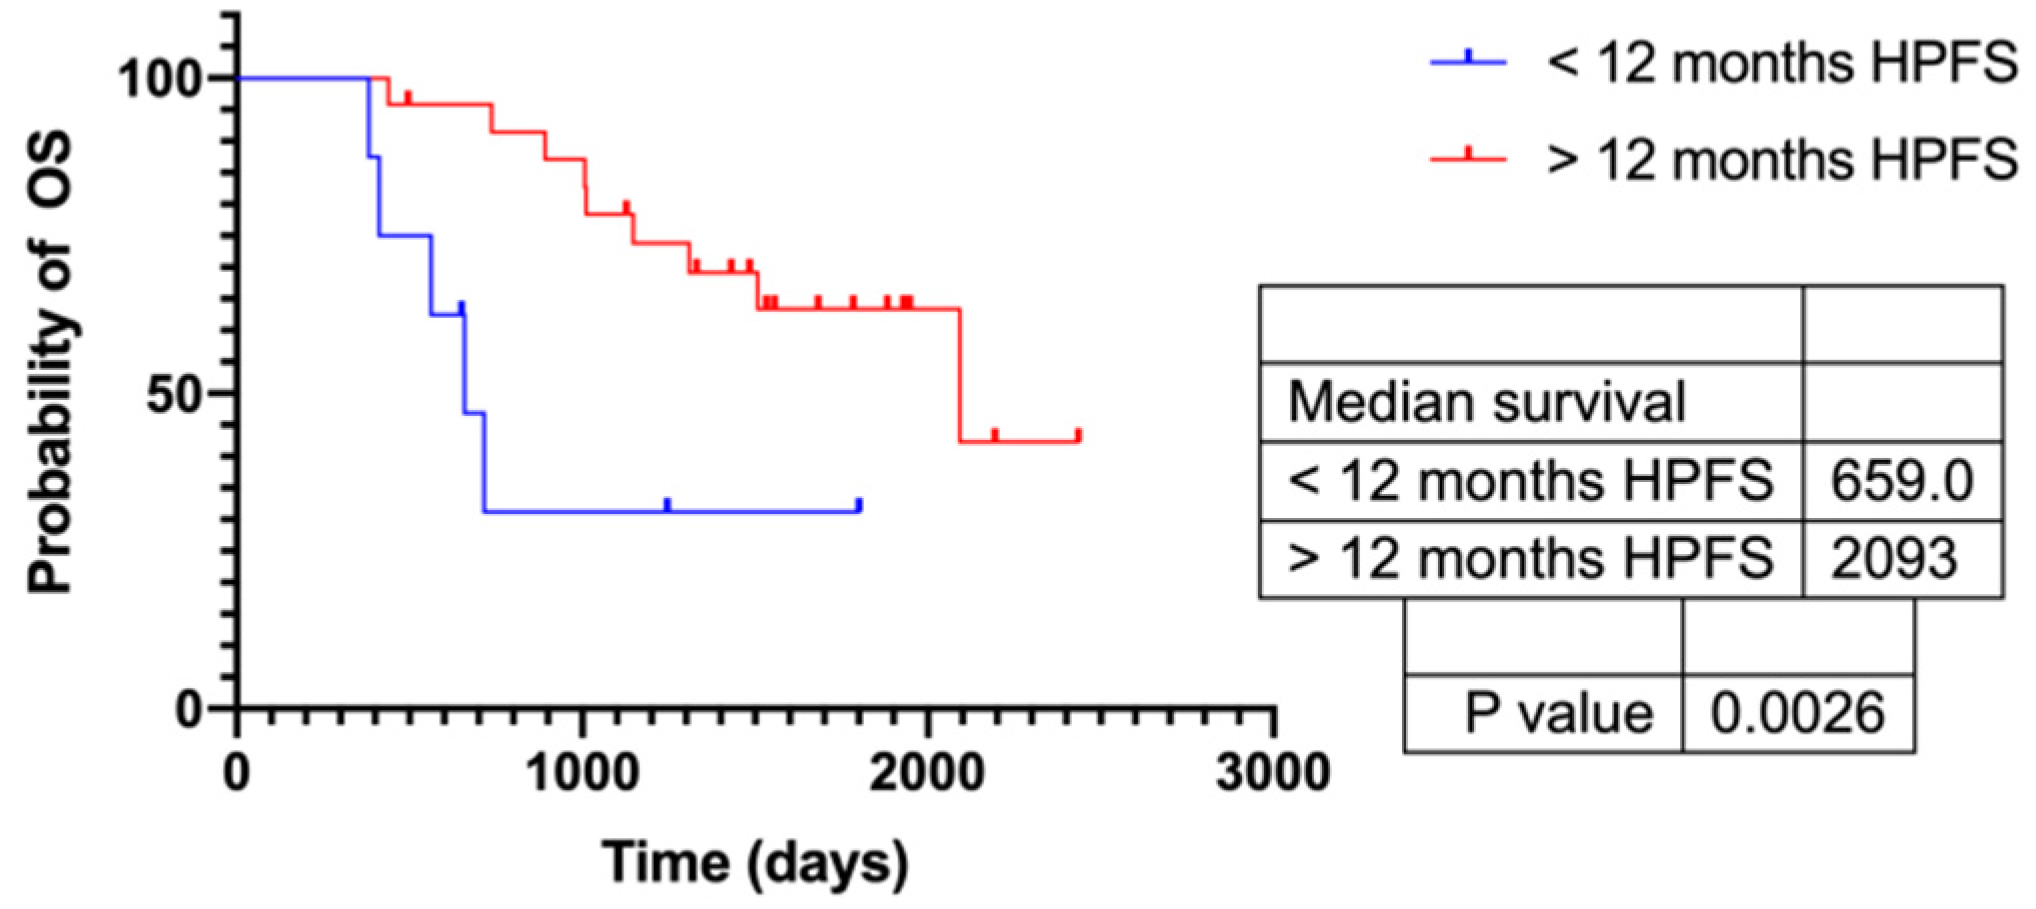

3.5. Response According to HPFS > 12 Months

3.6. Response According to HPFS > Median (720 d)